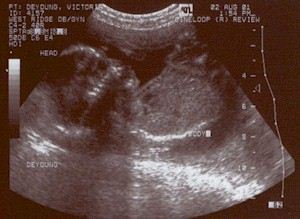

'Ultra' Holly! Holly (age: -4 months)